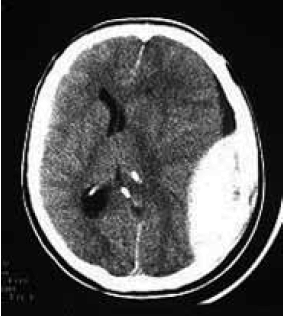

Homem de 43 anos dá entrada na emergência consciente e orientado, apresentando ferimento lacerocontuso em região parietal esquerda após sofrer queda da própria altura. Trazido pelo SAMU 192 (suporte básico) ao hospital, relatou que estava se sentindo bem, mas que não lembrava do que havia acontecido. Duas horas após sua admissão, enquanto aguardava realização de exames, o paciente perdeu a consciência. Na reavaliação do paciente, abertura ocular aos estímulos dolorosos, resposta verbal com sons incompreensíveis e resposta motora com reflexo de retirada; pupilas anisocóricas. Tomografia de crânio demonstrada.

Qual o provável diagnóstico e a topografia anatômica da lesão?